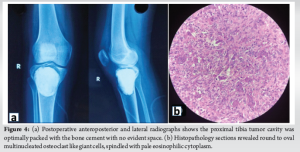

Post-operative anteroposterior and lateral radiograph (Fig. 4a) had shown that the proximal tibia tumor cavity was optimally packed with the bone cement.

Histopathology section (Fig. 4b) revealed round to oval multinucleated osteoclast like giant cells, spindled with pale eosinophilic cytoplasm these features were strongly suggestive of GCT.